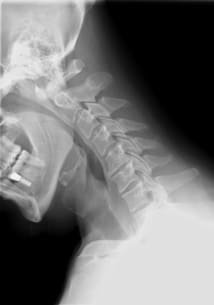

Diagnostic des zygapophyses cervicales : enfin des tests cliniques performants